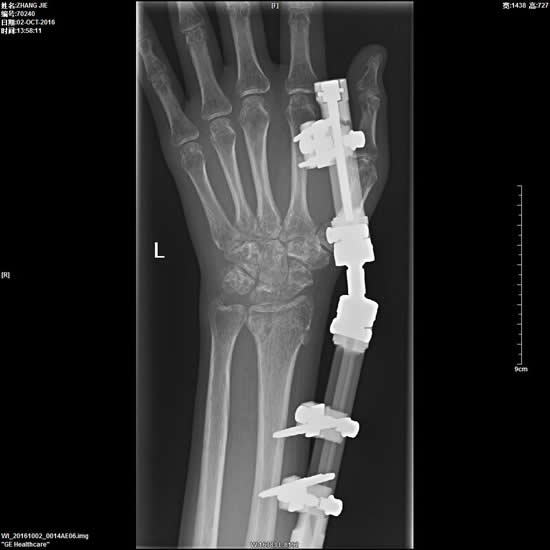

2、外固定架治疗四肢骨折。

3、复杂性关节内骨折的内固定手术。

6、四肢骨折的复位内固定术。